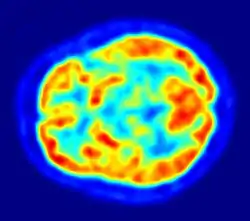

La biologie concerne les données moléculaires à partir de gènes à l’expression spécifique dans la cellule. La médecine et l'anatomie se rapportent à la structure de l'anatomie et des synapses des systèmes cérébraux. L’ingénierie - électrophysiologie comprend de simples canaux jusqu’aux électroencéphalographies sur la surface complète du cuir chevelu, ou encore l'imagerie cérébrale. L’informatique recouvre les bases de données, les logiciels, les sciences mathématiques. La chimie étudie des modèles de neurotransmetteurs, etc. Les neurosciences utilisent toutes les études expérimentales et théoriques susmentionnées pour comprendre le fonctionnement du cerveau à travers ses différents niveaux. Les spécialistes médicaux et biologiques aident à identifier les types de cellules uniques, leurs caractéristiques et les connexions anatomiques. La fonction et les structures de molécules organiques complexes, y compris une myriade de mécanismes biochimiques, moléculaires, génétiques et qui régissent le fonctionnement du cerveau sont déterminés par des spécialistes en chimie et en biologie cellulaire. L'imagerie cérébrale détermine l'information structurale et fonctionnelle pendant l'activité mentale et comportementale. Les spécialistes en biophysique et en physique sont responsables de l'étude de la physiologie des cellules neurales dans des réseaux neuronaux. Les données de ces domaines de recherche sont analysées et disposés dans des bases de données et des modèles neuronaux afin d'intégrer divers éléments dans un système sophistiqué. La neuro-informatique est donc le point de rencontre de nombreuses disciplines.

- Gary Egan, neuro-imagerie et neuro-informatique, Howard Florey Institute, Université de Melbourne, Melbourne, Australie. Scientifiques de l'Institut utilisent des techniques d'imagerie du cerveau, telles que l'imagerie par résonance magnétique, pour révéler l'organisation des réseaux cérébraux impliqués dans la pensée humaine.